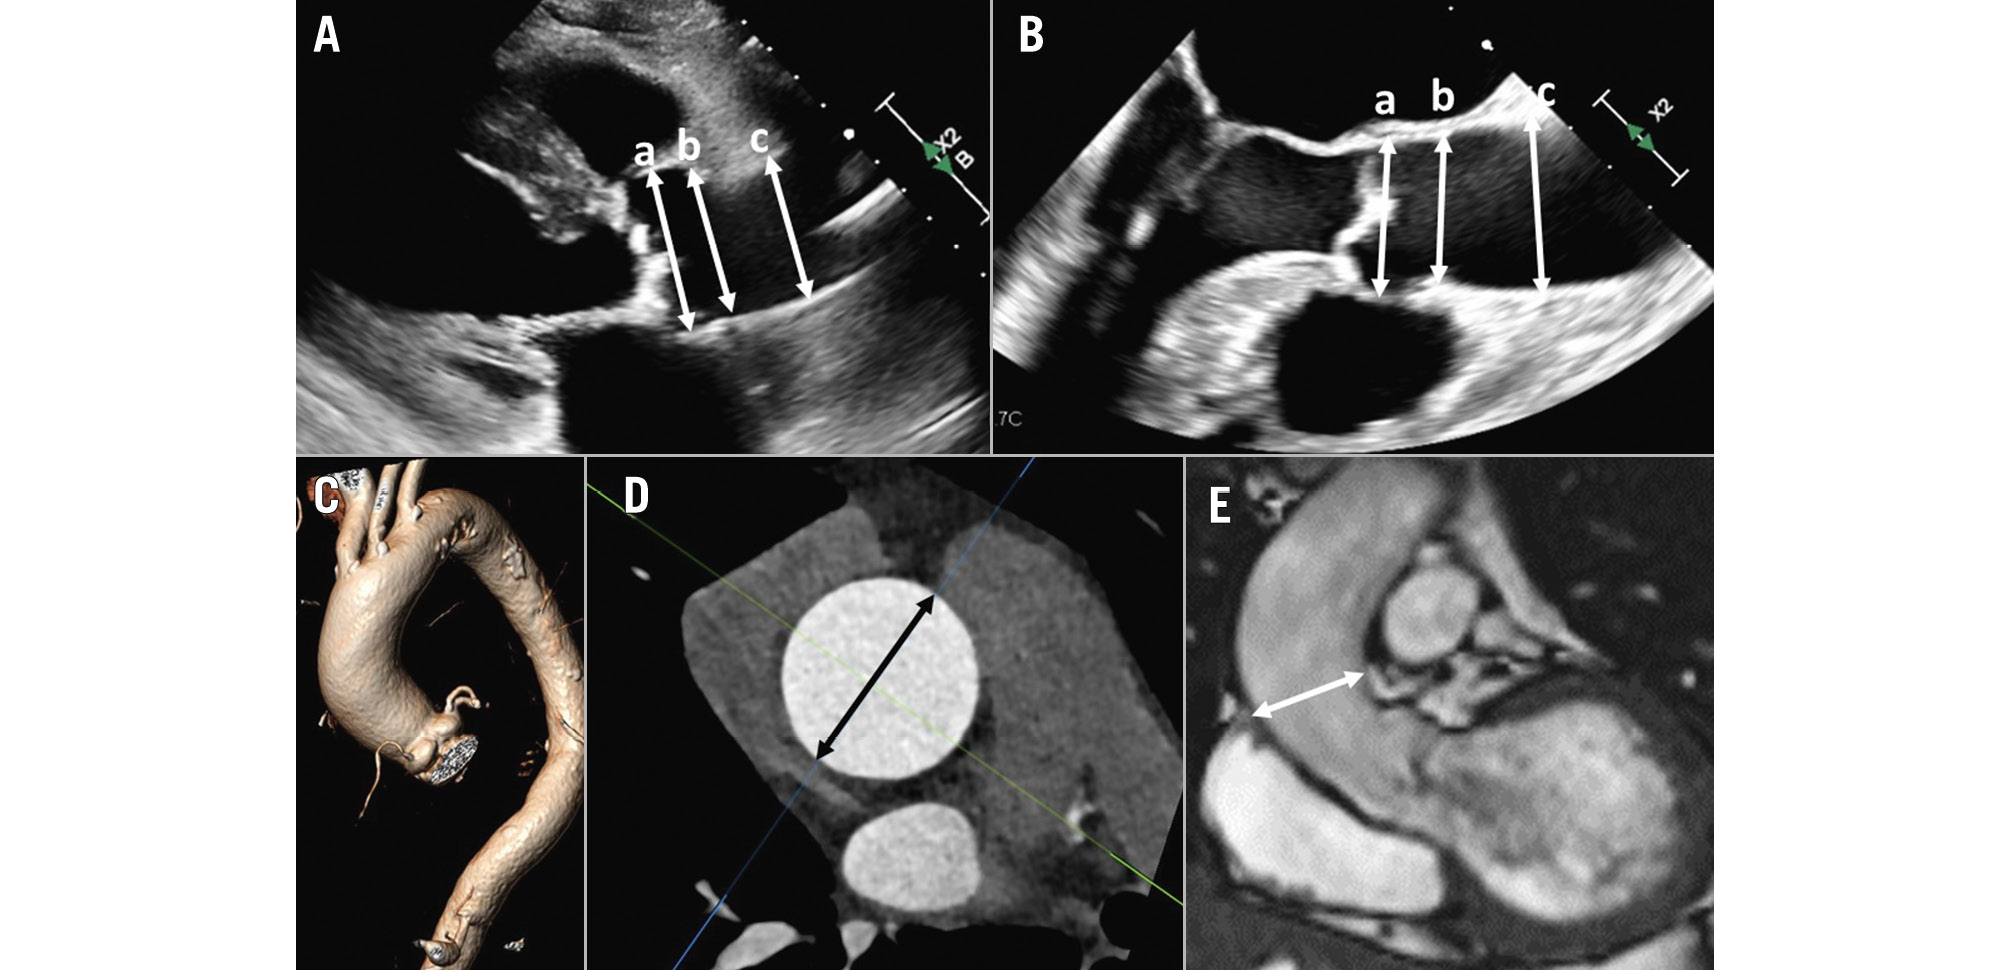

ASSESSMENT OF THE AORTIC ROOT AND ASCENDING AORTA

Aortic root and ascending aortic dimensions are systematically underestimated when using inner-to-inner edge measurements and may be underestimated when using two-dimensional (2D) echocardiography, as the true long axis of these structures may not be shown (Figure 3). When using 3D techniques, the cross-sectional area of the ascending aorta and sinotubular junction can be reconstructed with multiplanar reformation planes, and the measurement of the dimensions of these structures is more accurate than when measuring them from the axial views (Figure 3). The sinus of Valsalva and the ventriculo-aortic junction (aortic annulus) do not show a circular shape, and therefore, the measurement is better performed from the true cross-sectional area obtained from 3D multiplanar reformation planes. The 2D echocardiographic measurements from the left parasternal long-axis view using the leading-to-leading edge correlate with the sinus-to-sinus inner-to-inner edge measurements obtained with CT or CMR. For the ventriculo-aortic junction (aortic annulus), the cross-sectional plane obtained with 3D-imaging techniques allows the measurement of the maximum and minimum diameters, the perimeter and the area, which are key for the selection of the prosthesis size (Figure 4)678. The 2D echocardiographic diameter of the aortic annulus is usually concordant with the minimum diameter obtained with 3D-imaging techniques (Figure 4).

Figure 4. Measurement of the aortic annulus. Aortic annulus measurement with 3-dimensional echocardiography (A) and computed tomography (B). The multiplanar reformation planes are aligned across the aortic annulus bisecting the nadir points of the aortic cusps. The aortic annulus area is then planimetered (dotted line).